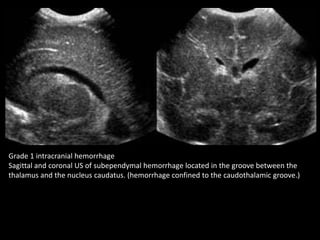

Grade 1 intracranial hemorrhage

Sagittal and coronal US of subependymal hemorrhage located in the groove between the

thalamus and the nucleus caudatus. (hemorrhage confined to the caudothalamic groove.)

Grade 1 intracranialhemorrhage Sagittal and coronal US of subependymal hemorrhage located in the groove between the thalamus and the nucleus caudatus. (hemorrhage confined to the caudothalamic groove.)